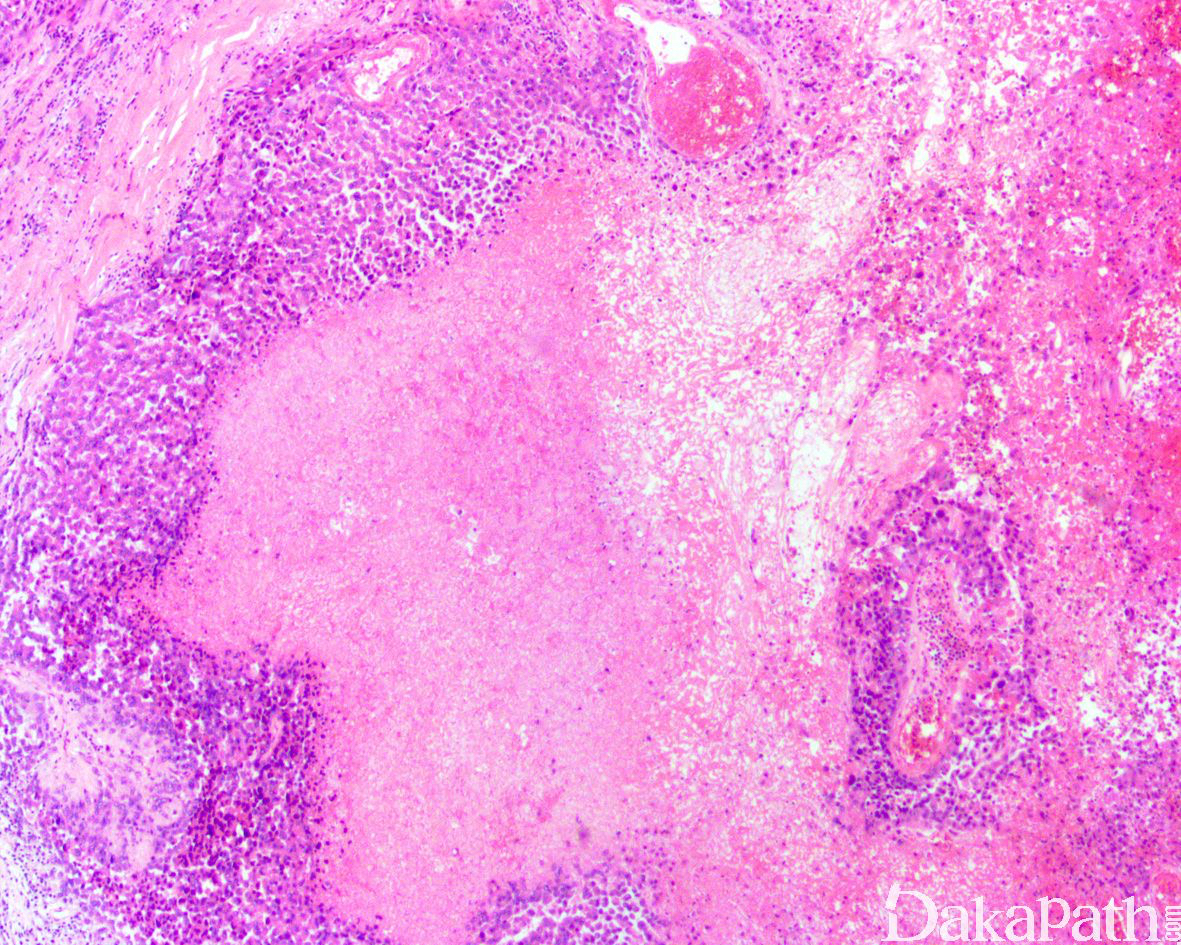

瘤细胞呈结节状或花环样排列,结节周围围绕胶原纤维,结节中央常伴有坏死;

肿瘤由上皮样细胞和梭形细胞共同组成,上皮样细胞呈多边形、卵圆形或胖梭形,胞质丰富,深嗜伊红色,和梭形细胞间有移行;细胞核轻度异型,呈空泡状,可见小核仁,核分裂像通常少于 5/10HPF;

间质可见嗜伊红色的胶原纤维;